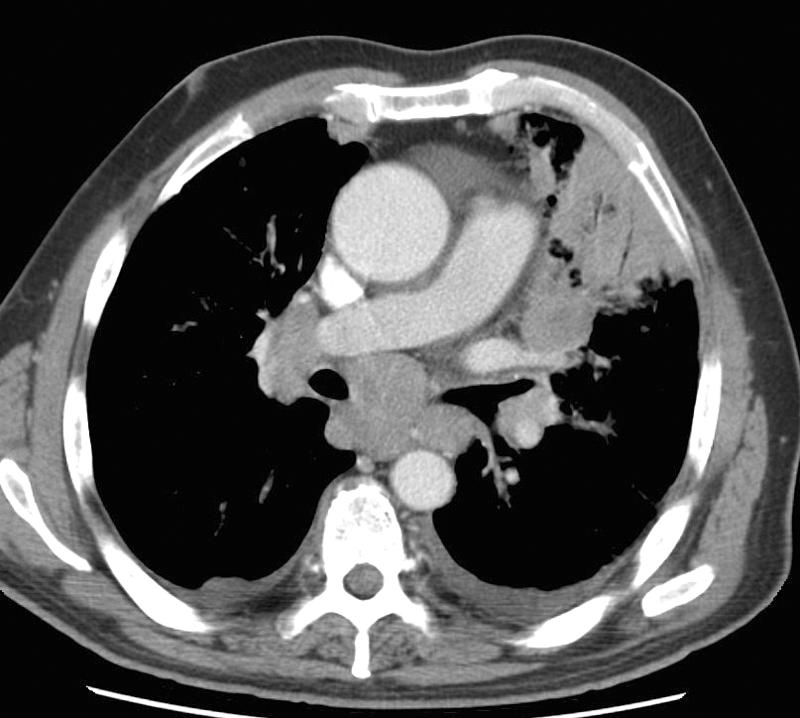

Gallery Lung Cancer Mets RCC a

RCC a